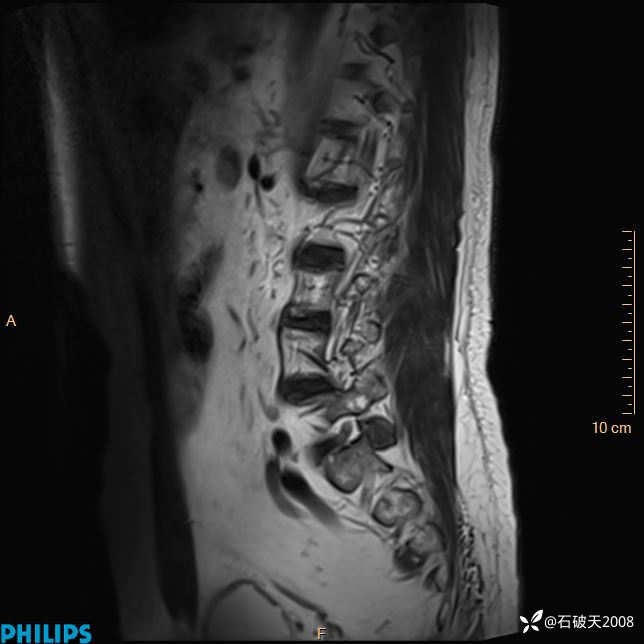

2023年3月份MRI影像

T2矢状位压脂